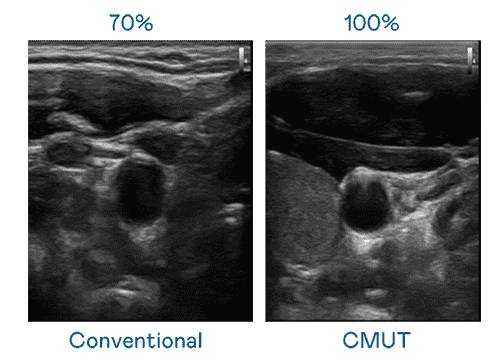

CMUT 技术是一种用电容式微机电元件来产生超音波讯号的技术。。与传统 PZT 压电式技术相比,,,CMUT 频宽增加 30%,,更宽频的超音波讯号让影像解析度大幅提升,,,,是实现高影像品质医疗超音波扫描、、、、促进精准医疗发展的关键技术。。。。

大频宽带来超清晰影像

超音波影像的解析度高低,,首先取决于探头能发出的讯号频宽。。尊龙集团 CMUT 可提供高清晰的超音波讯号,,提供高频宽、、、高灵敏度、、影像纹理细节更高的超音波影像,,,协助医护人员缩短影像判读时间及利用精准的医疗影像进行诊断。。